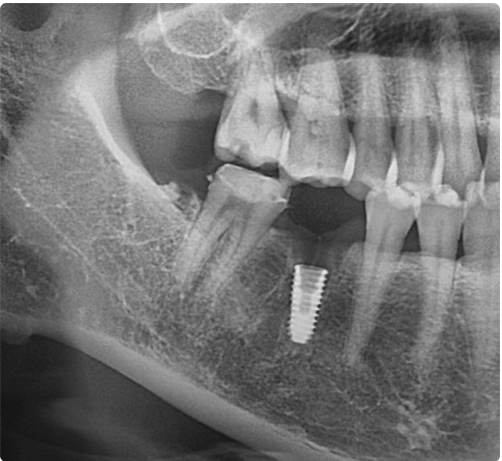

다음은 같은 날 방문하셨던 또 다른 환자분의 사례입니다.

두 번째 환자분은 눈으로 보아도 치아가 갈라진 부위를 확인할 수 있는 상태였습니다.

파절 범위가 비교적 뚜렷했고, 환자분께서도 강한 통증을 호소하셨습니다.

이미 손상이 많이 진행된 상황이어서 치아를 보존하기는 어려웠고, 결국 발치 후 임플란트 치료를 계획하게 되었습니다.